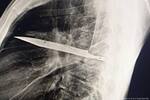

El adolescente, quien vestía una camiseta amarilla y jean, descendió del vehículo e intentó hablar con ellos para que lo dejaran tranquilo. Pero los atacantes ya tenían un objetivo claro y enseguida, los dos parrilleros se le fueron encima y lo agredieron con un machete y un cuchillo.

Mientras los bandidos escapaban, el hombre subió a su hijo a la moto y lo llevó a toda marcha hacia un centro médico.

“Se metió en contravía, se pasó los pares y hasta se estrelló con una patrulla. Actualmente él está estable, a la espera de una cirugía”, agregó.